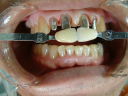

下顎前歯切端を内側に削って頂いた所 |

☆下顎前歯の切端を削って頂ければ

2〜2を内側に入れて審美的にも納得して

頂ける補綴物が出来ると思われます。